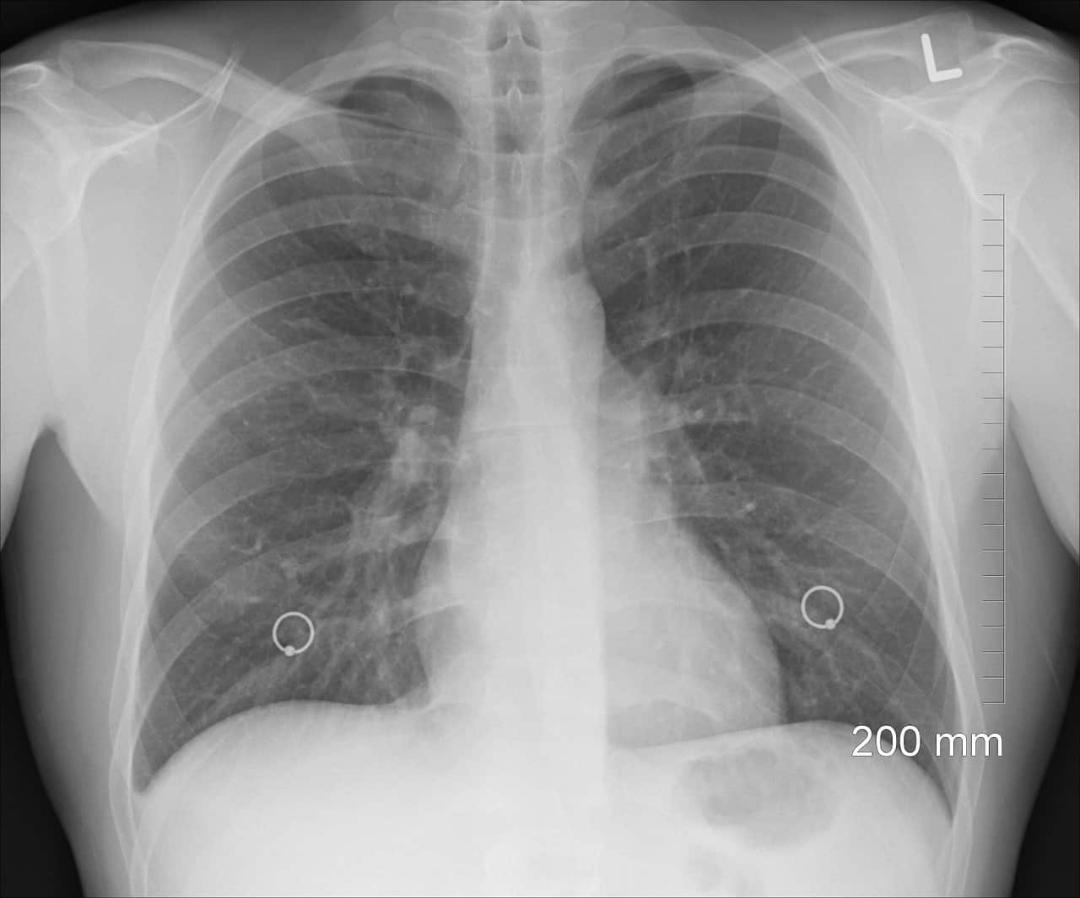

[Figure, Bullous emphysemabilateral Image courtesy S Bhimji MD Is Bullous Emphysema Fatal Keep reading to learn more,. Like other forms of emphysema, bullous emphysema (be) can cause difficult and painful breathing. Your guide to bullous emphysema (be) and its treatment like other forms of emphysema, bullous emphysema (be) can cause difficult and painful breathing. Symptoms may include shortness of breath, coughing, and wheezing, indicating potential lung complications. Eighty percent of patients presenting. Is Bullous Emphysema Fatal.